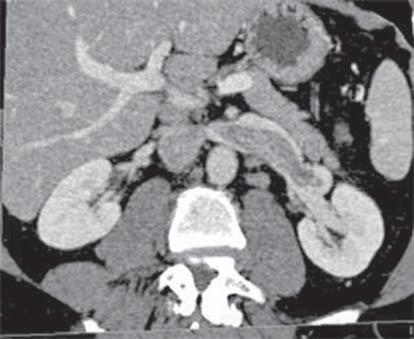

Une radiographie et un scanner du thorax sont

D aspect typique d'œdème pulmonaire aigu E